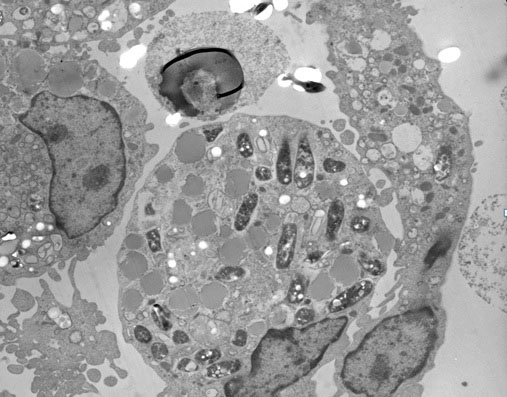

Para replicar la formación de los granulomas en un modelo in vitro, se infectaron PBMCs humanas con M. tuberculosis H37Ra o BCG, y seguidamente se incubaron por 5 días. A las 24 h de incubación, las PBMCs tendieron a formar agregaciones celulares de linfocitos en presencia de H37Ra (Fig. 1A) o BCG (Fig. 1B). Las muestras controles correspondientes de los mismos donadores cultivadas en presencia de Escherichia coli ATCC 25922 o Staphylococcus aureus ATCC 25923, o cultivadas en ausencia de bacterias no formaron estos agregados (Figs. 1C, 1D, 1E) indicando que los agregados celulares se forman específicamente en respuesta a la infección con micobacterias. Estas acumulaciones celulares con forma similar a los granulomas, fueron confirmadas mediante tinción Wright-Giemsa a las 24 h siguientes a la infección con M. tuberculosis H37Ra (Fig. 1F). La microscopía de transmisión electrónica de estos agregados evidenció el atrapamiento de las micobacterias por los fagocitos presentes en las agregaciones celulares a las 48 h post-infección (Fig. 2). Las estructuras granulomatosas formadas in vitro persistieron por 96 h, y luego comenzaron a desvanecerse.

Figura 2.

Microscopía de Transmisión electrónica de un granuloma inducido por H37Ra. Después de 48 h siguientes a la infección, las agregaciones celulares fueron recolectadas, fijadas y embebidas en una resina de Epon-araldite. Secciones de 0.5 µm fueron obtenidas, teñidas y observadas bajo microscopio de transmisión electrónica (x4,000). Se pueden observar múltiples vesículas fagosomales conteniendo la bacteria H37Ra.